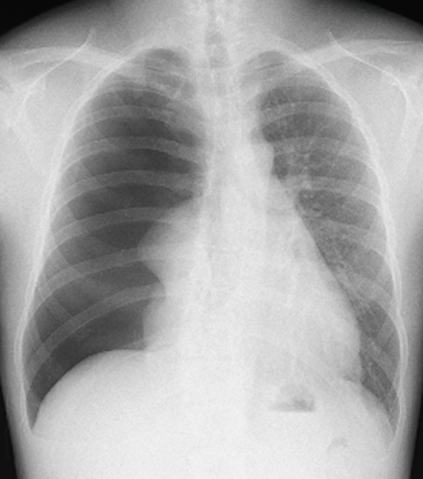

X-p:

右肺は高度虚脱。

縦隔の左方変位。

右緊張性気胸の診断。